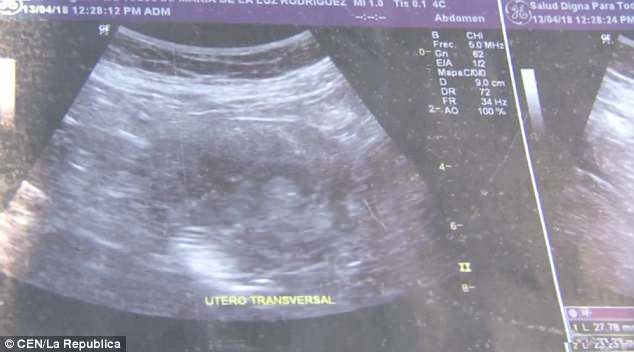

70歲的墨西哥婦人Maria de la Luz聲稱自己現懷有6個月身孕,並展示超聲波掃描照片,表示她確實懷有一名女嬰。倘若屬實,Maria de la Luz將成為全世界最年長的孕婦,比現有紀錄保持者年長4年。

Maria de la Luz說:「當時我嘔吐、頭暈和腳痛,在私人診所和公立醫院前後做了10次左右的超聲波掃描,醫生亦不敢相信我懷孕。」